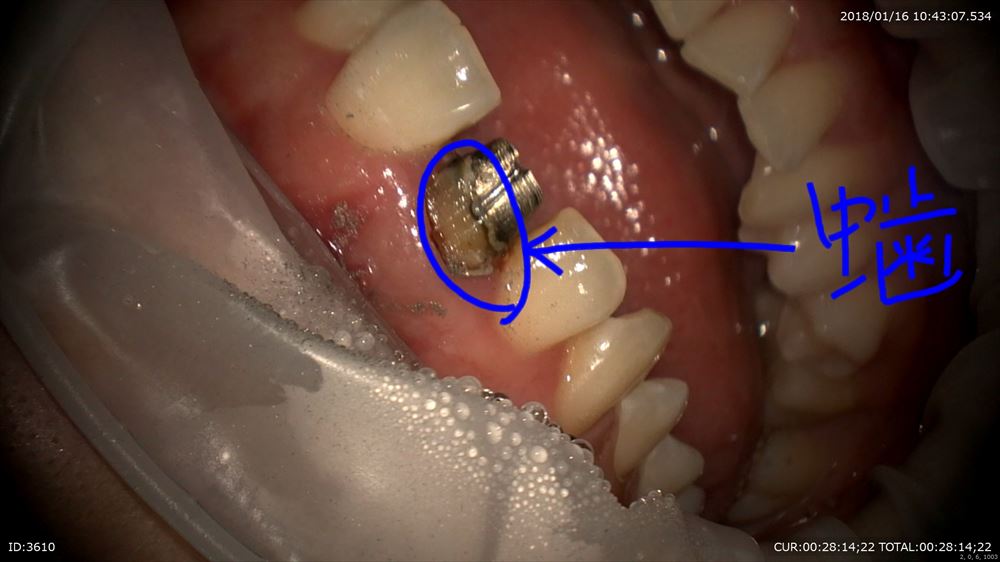

中はこんなに汚れています。

ここから精密な仮歯をオーダーメイドで作成。既成冠なんてだめです。

なるべく質感も同じにして前方のガイドもしっかりつけないといけないから。オーダーメイドの仮歯。

裏側もチエック。フィットOK。

これで準備完了。次回から精密根管治療スタート!